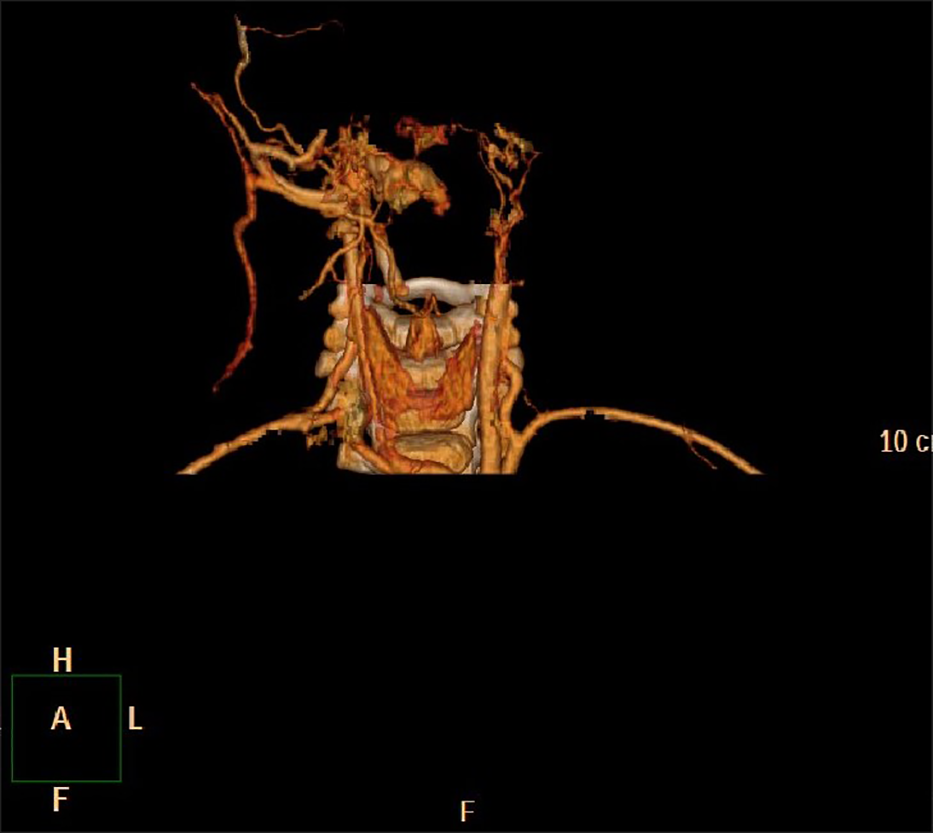

Figure 2

No. 8 patient 3D reconstruction of subacoustic hemangioma before treatment.